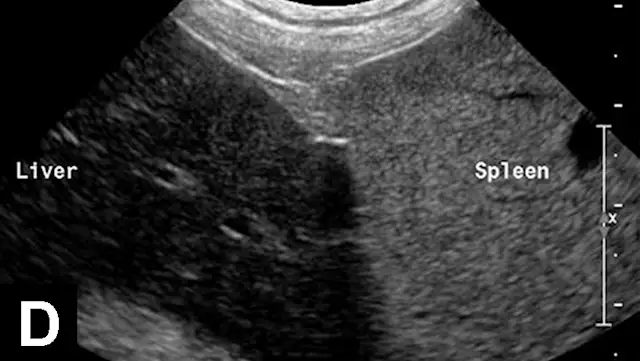

In each of these cases, histologic diagnosis was made using fine-needle aspirates of the liver (vacuolar hepatopathy, hepatic lipidosis, acute severe neutrophilic hepatitis, respectively). Transverse image (A) of the left side of the liver in a normal dog showing hepatic vein (arrows) and portal vein (arrowheads). Hyperechoic liver (B) secondary to glycogen accumulation resulting from Cushing’s disease in a dog. Note the decrease in portal vascular markings. Hyperechoic and hyperattenuating liver (C) secondary to hepatic lipidosis in a cat. Note the hypoechoic falciform fat in the near field (≤1.5 cm deep) relative to liver echogenicity. In addition, there are some contact artifacts resulting in hyperechoic lines as well as the normal lines of abdominal musculature in the extreme near field (<0.5 cm). In normal cats, falciform fat and hepatic echogenicity are isoechoic to each other. In the far field, hyperattenuation of the ultrasound beam results in image dropout (starting at a depth of 3.5 cm). Hypoechoic liver (D) secondary to acute hepatitis in a dog. Note the marked decrease in echogenicity relative to the spleen.